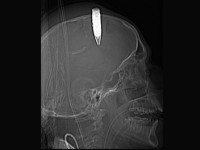

Një ushtar afgan i është nënshtruar një operacioni tepër delikat prej 5 orësh, për të hequr nga pjesa e sipërme e kafkës një plumb shpërthyes, që mund të plaste në çfarëdo momenti, edhe gjatë ndërhyrjes.